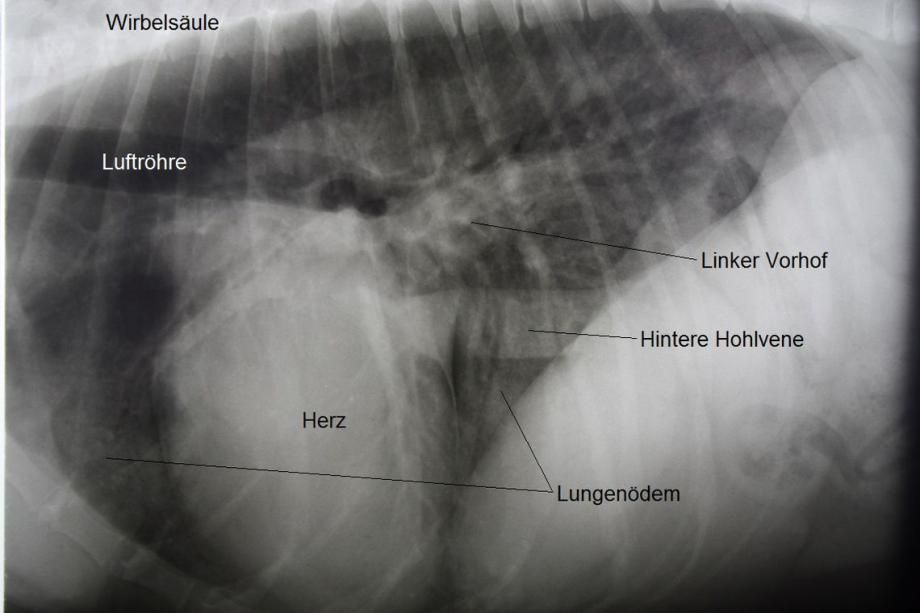

Weiterer Untersuch: Bruströntgen

Radiologisch wird schnell klar, weshalb der Hund verstärkt atmet: Weite Teile der Lunge scheinen diffus verdichtet (d.h. weiss); Art und Verteilung der Veränderungen sprechen für eine Ansammlung von Flüssigkeit in der Lunge, ein Lungenödem. Die Herzsilhouette ist ausserdem vergrössert, insbesondere die linke Herzkammer und der linke Herzvorhof erscheinen erweitert.